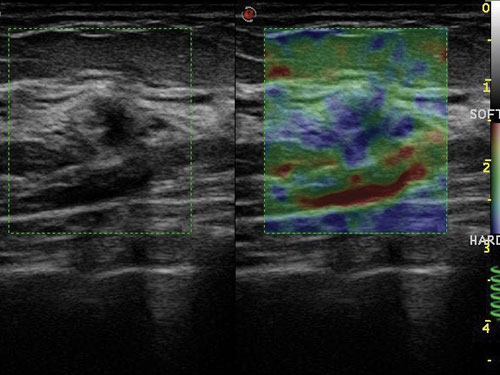

ElaXto: ElaXto je neinvazivní metoda, která pomáhá lékařům při hodnocení elasticity tkáně. Rozdíly v tkáňových reakcích jsou detekovány a vizualizovány v reálném čase.